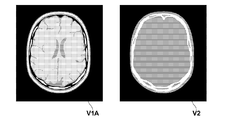

- the image deformation amount estimation unit 12 evaluates the similarity between the deformed first image V1a and the second image V2 by using an evaluation function S expressed by the following equation (3).

- the value of the evaluation function S increases as the pixel value distribution of the deformed first image V1a and the second image V2 is similar.

- the image generation unit 14 generates an image V1A obtained by converting the first image V1 using the conversion function determined by the image deformation amount estimation unit 12.

- FIG. 2 is a flowchart illustrating a processing flow of the image processing apparatus according to the second embodiment. The processing flow will be described with reference to FIG. First, the image acquisition unit 11 acquires a first image (first image data) V1 and a second image (second image data) V2 obtained by imaging a subject (S01).

- the image generation unit 14 converts and reconstructs the first image using the determined conversion function, and generates the image V1A (S08). Then, the display control unit 15 displays the generated image V1A and the second image V2 side by side so that they can be compared (S09).